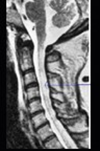

131、单项选择题

患者,女性,23岁,11天前出现发热、头痛和全身酸痛,近两天出现颈背疼痛,四肢无力,查体四肢肌张力低,腱反射消失,病理征(-),C平面以下痛觉减退,尿潴留,行颈髓MRIT2加权像出现如图所示病变。最可能的诊断是()